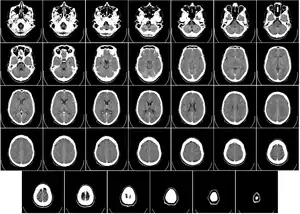

頭部

主要用來診斷腦部血管病變以及顱內出血,檢查不一定要用到顯影劑。在病人有急性中風的情形下,它雖然沒辦法排除血管阻塞的可能性,但是可以排除出血的可能性。如此一來,抗凝血劑就可以大膽地應用。在診斷腫瘤的應用上,電腦斷層配合靜脈顯影的檢查並不常用,而且效果也比核磁共振影像(MRI)差。它也可以用來診斷顱內壓是否有增加,例如要做腰椎穿刺或是評估腦室腹腔分流術時。

X射线计算机断层成像在診斷有外傷的顱骨及顏面骨的骨折也有很大的用處。在頭頸口的部位,對於頭骨和顏面骨或是牙齒的畸形,它有術前評估的作用;下顎、副鼻竇、鼻腔,眼框等部位所生囊腫或是腫瘤的評估;慢性鼻竇炎成因的診斷;還有植牙重建的評估。